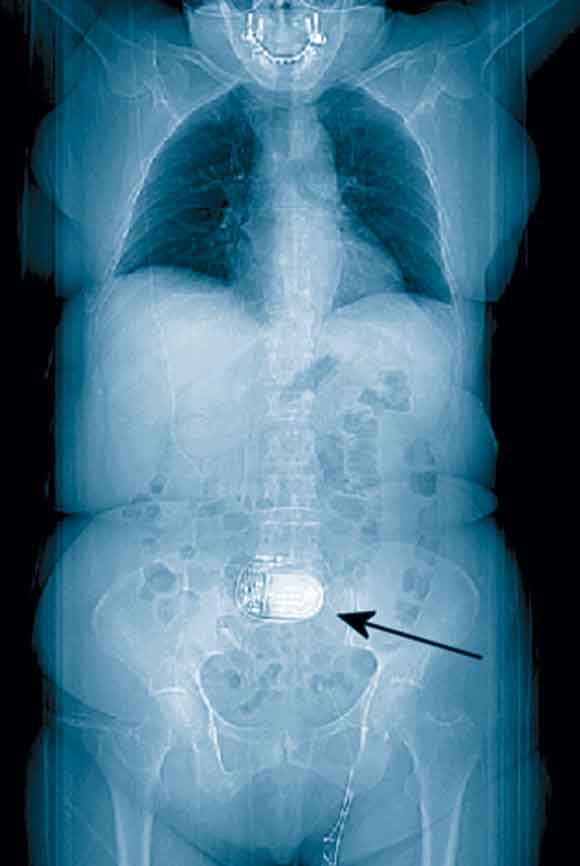

Review of the patient’s previous medical records revealed, on a thoracoabdominal image derived from computed tomography data, a foreign body in the central abdominal region (Box 2). Questioning of the patient after the angioplasty revealed that this was an electrostimulator (Itrel II, Medtronic, Minneapolis, USA) implanted a few years earlier as part of a dynamic graciloplasty to treat faecal incontinence. An ECG performed 12 hours after the angioplasty with the device deactivated (by the patient’s control programmer) produced an ECG tracing free of artefacts (Box 1B).

Intrathoracic devices are usually discovered on physical examination or standard chest x-ray, but devices in other parts of the body may not be obvious. In dynamic graciloplasty to treat anal incontinence, the gracilis muscle is transposed around the anal canal and electronically stimulated by a device placed in a subcutaneous pocket in the abdominal wall.4 In our case, this device led to ECG artefacts potentially interfering with the ability to diagnose the acute myocardial infarction.